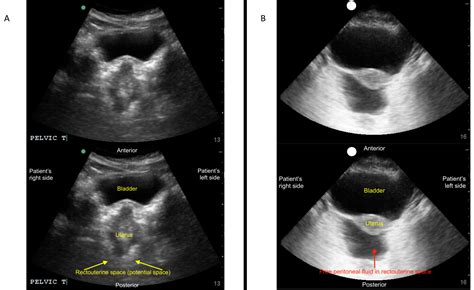

• EFAST (Extended Focused Assessment with Sonography for Trauma): This is a comprehensive ultrasound examination used to evaluate patients with trauma. It includes views of the heart, lungs, abdomen, and pelvis to detect fluid collections, pneumothorax, and other injuries.

• Focused Abdominal Ultrasound: This evaluates the abdomen for free fluid, organomegaly, and other abnormalities.

• Trauma Assessment: In trauma patients, the Fast Exam Ultrasound helps identify internal injuries, such as hemoperitoneum, hemothorax, and pericardial effusion.

• Abdominal Evaluation: It helps identify free fluid in the abdomen, organomegaly, and other abnormalities.